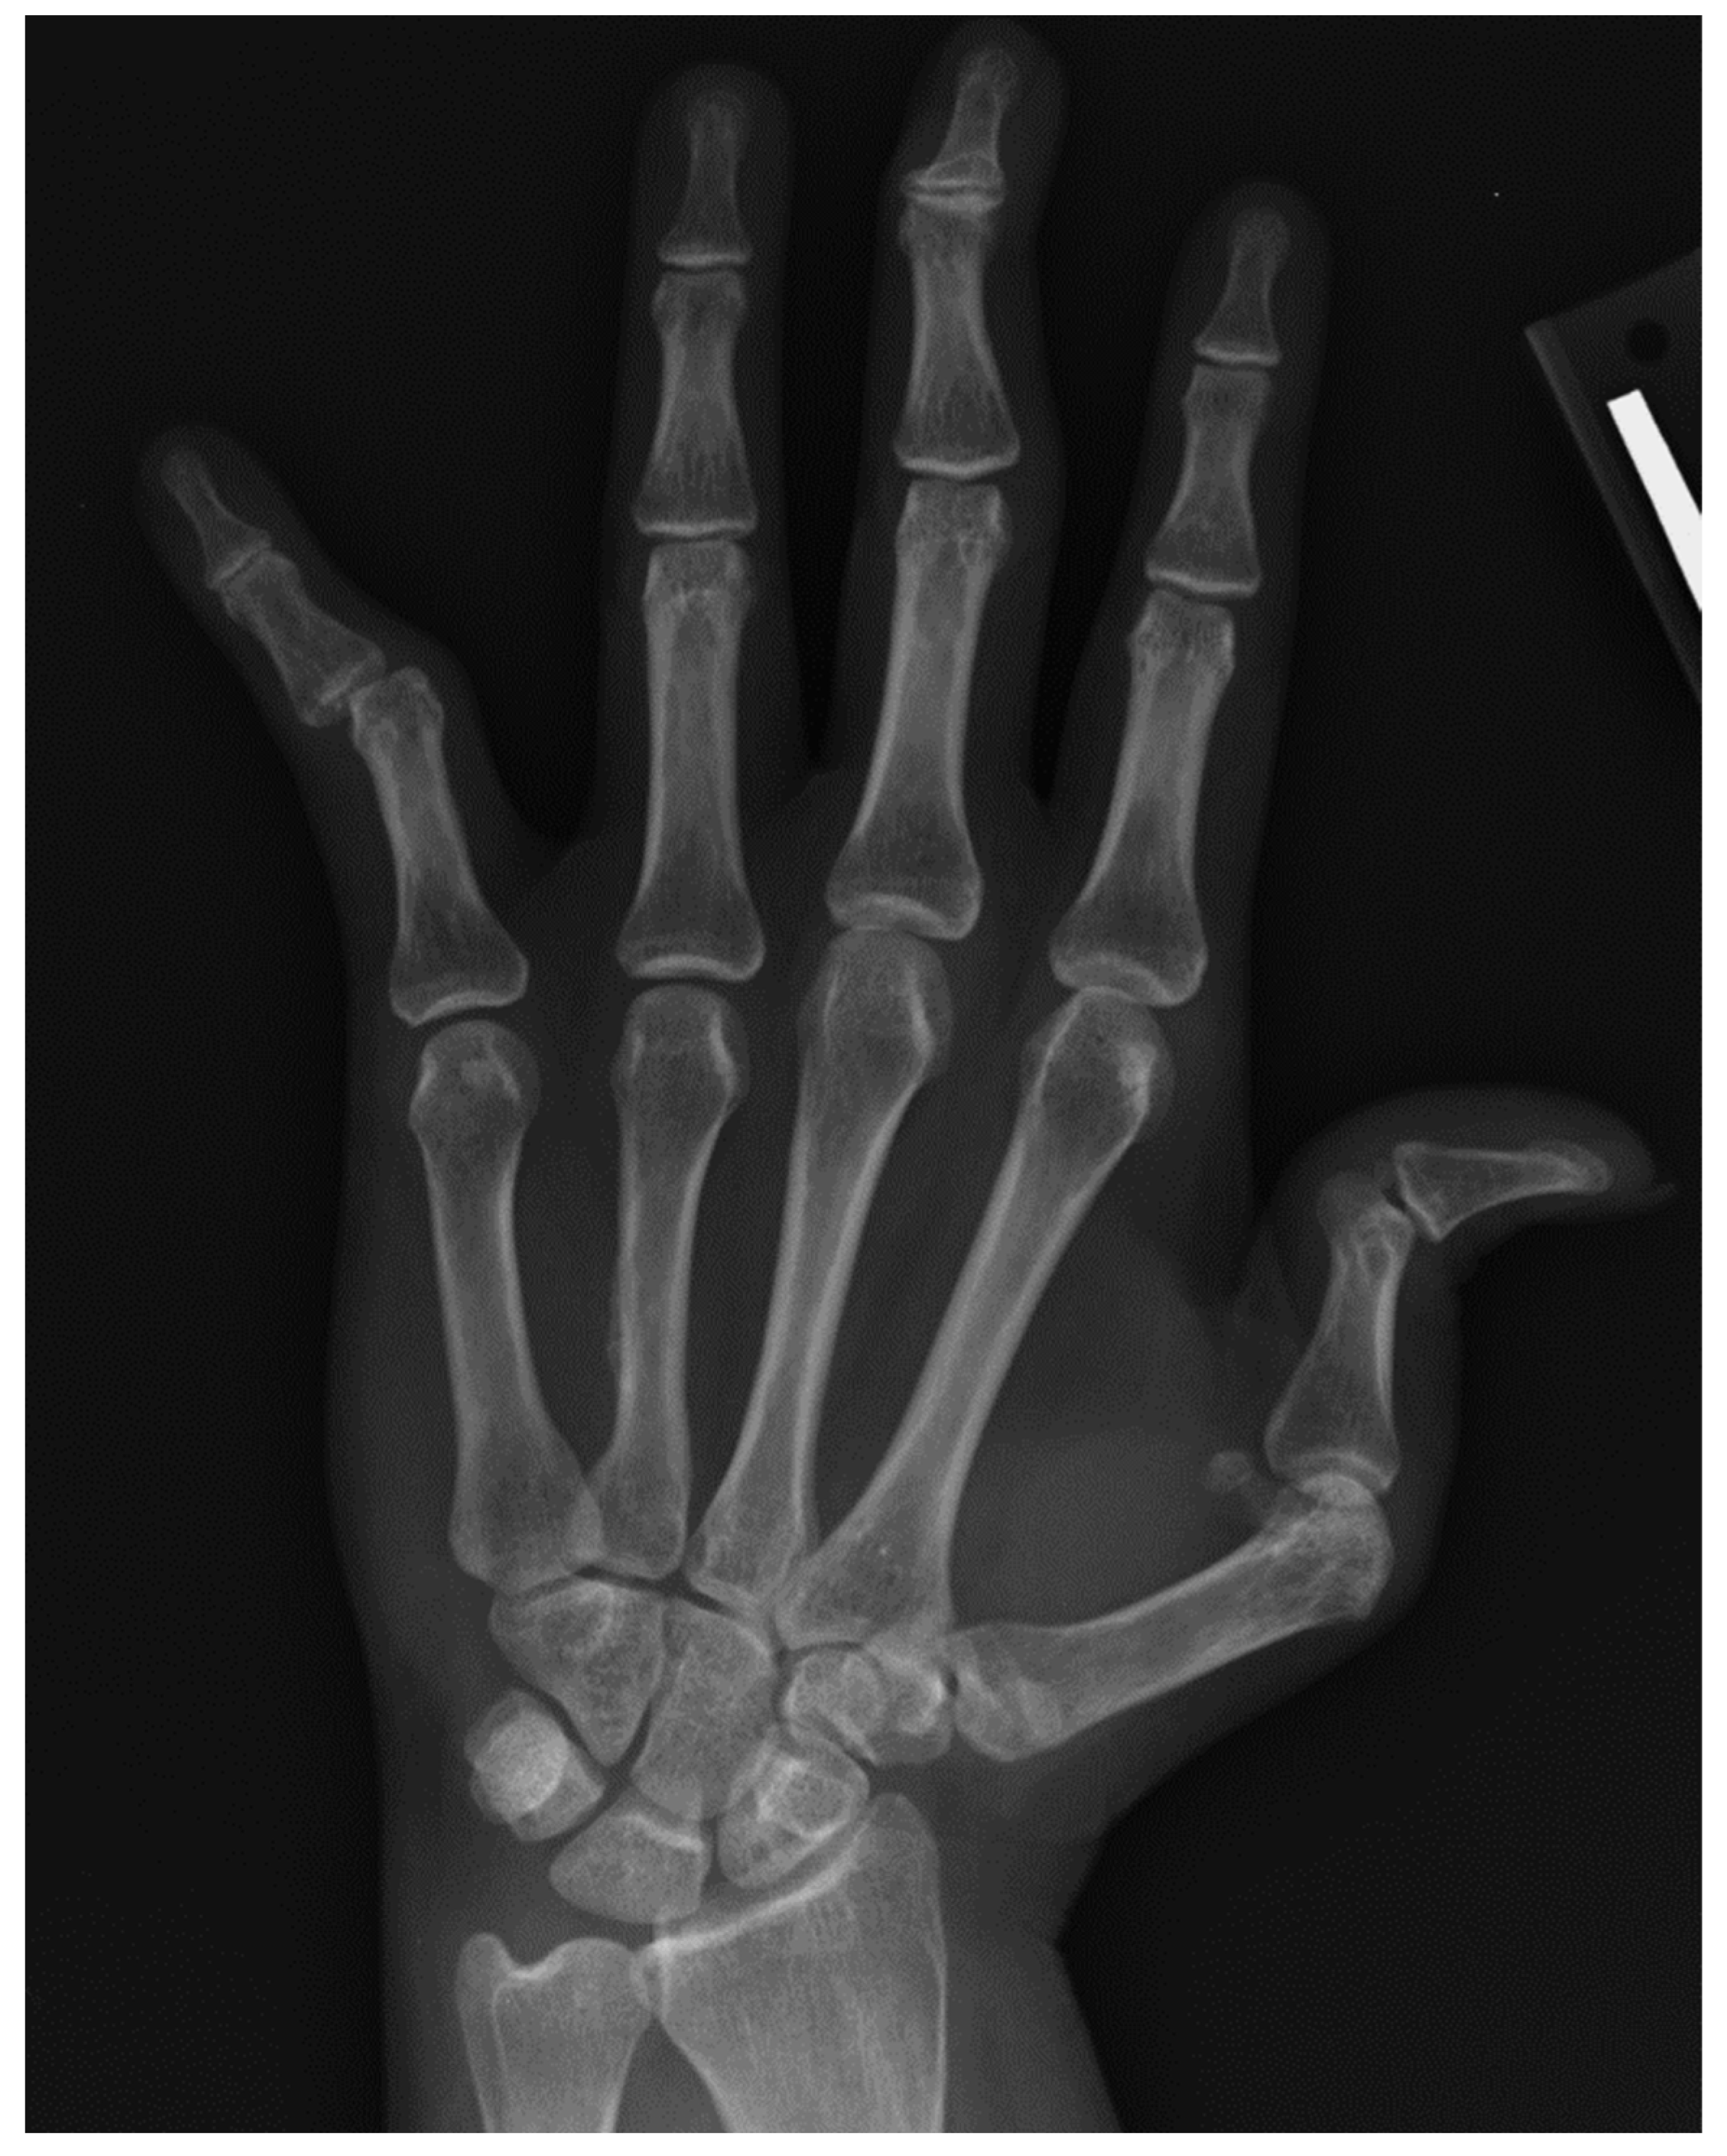

4. Rheumatoid Arthritis